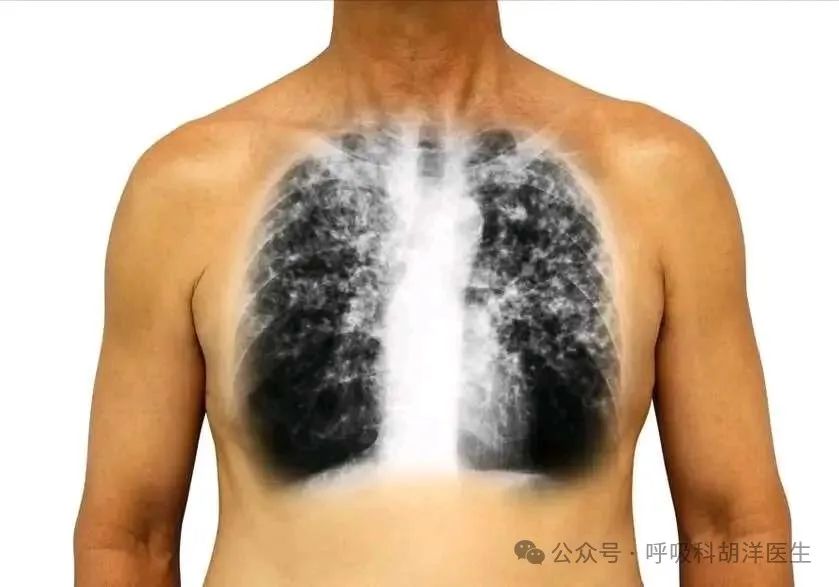

病床上一位瘦骨嶙峋的老人可以走路,但他的健康状况太差了。他走路时颤抖着。他去医院住下,拍了一张CT照片。他的半肺几乎被破坏了。他有一个白色的肺,里面有一个大洞和一个小洞。他换了很多痰,主要是白痰。有时他会有黄痰。在家治疗一个月没有效果。他的家人说他已经检查了所有的检查,但他找不到任何原因。